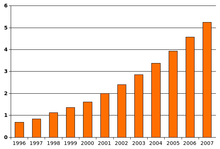

Autism has a strong genetic basis, although the genetics of autism are complex and it is unclear whether ASD is explained more by rare mutations, or by rare combinations of common genetic variants. In rare cases, autism is strongly associated with agents that cause birth defects. Controversies surround other proposed environmental causes, such as heavy metals, pesticides or childhood vaccines; the vaccine hypotheses are biologically implausible and lack convincing scientific evidence. The prevalence of autism is about 1–2 per 1,000 people worldwide, and the Centers for Disease Control and Prevention (CDC) report 11 per 1,000 children in the United States are diagnosed with ASD as of 2008. The number of people diagnosed with autism has increased dramatically since the 1980s, partly due to changes in diagnostic practice; the question of whether actual prevalence has increased is unresolved.

Most recent reviews tend to estimate a prevalence of 1–2 per 1,000 for autism and close to 6 per 1,000 for ASD, and 11 per 1,000 children in the United States for ASD as of 2008; because of inadequate data, these numbers may underestimate ASD's true prevalence. PDD-NOS's prevalence has been estimated at 3.7 per 1,000, Asperger syndrome at roughly 0.6 per 1,000, and childhood disintegrative disorder at 0.02 per 1,000. The number of reported cases of autism increased dramatically in the 1990s and early 2000s. This increase is largely attributable to changes in diagnostic practices, referral patterns, availability of services, age at diagnosis, and public awareness, though unidentified environmental risk factors cannot be ruled out. The available evidence does not rule out the possibility that autism's true prevalence has increased; a real increase would suggest directing more attention and funding toward changing environmental factors instead of continuing to focus on genetics.